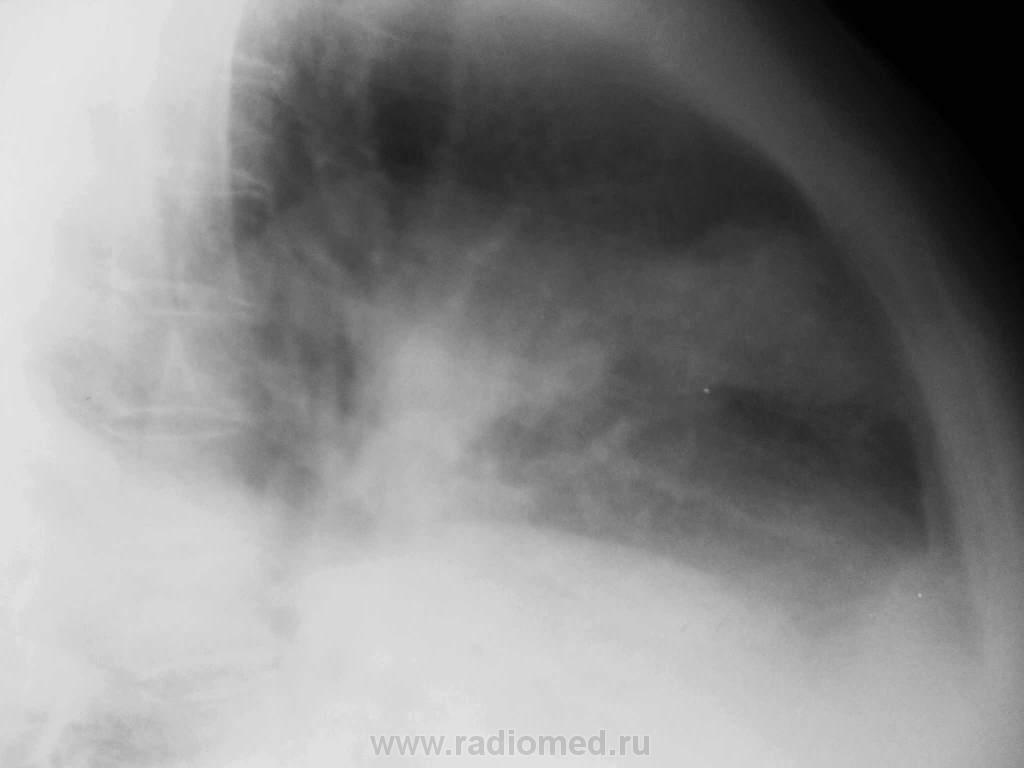

Женщина 62 лет, многие годы наблюдается кардиологом по поводу ИБС, мерцательная тахиаритмия, стенокардия. ПИКС (2005). Одышка, боли за грудиной. Неоднократно лечилась в стационаре. Несколько раз плевральные пункции. Ухудшение, очередная госпитализация. Как могла обработала снимки, простите за плохое качество. Ваше мнение, уважаемые коллеги?

9 января, после плевральной пункции, откачано 2,400 жидкости:

12 января, еще 1,600 откачано:

Сомневаюсь. Большой односторонний гидроторакс не характерен для кардиологических больных. Я бы написал "Большой правосторонний гидроторакс" и фсе. Больший результат даст лабораторное исследование пунктата.

Анализ плевральной жидкости: серозно-геморрагическая, нейтрофилы 40%, лимфоциты 60%, + клетки с признаками атипии, эрц 65-70

Цитология плевральной жидкости: лимфоциты, пролиферация мезотелия с атипией; единичные группы клеток, подозрительные на cr.

На 99% уверен что при контрастировании получите ТЭЛА и инфаркт пневмонию справа.

В этом случае я ОЧЕНЬ СИЛЬНО рекомендую сделать с контрастом. По тому как выглядят инфильтраты - очень сильное подозрение на то что имеет место быть ТЭЛА. - очень похоже на зоны инфарктов. Вероятнее всего хроническая, возможно на этом фоне острая "постреливает". ОБЯЗАТЕЛЬНО сделйте контраст. Больше пока ничего не посоветую :(